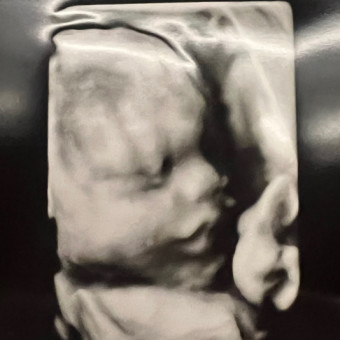

Hi all! 😊 Thank you for visiting my baby registry for sweet baby Gianna. We are so grateful for all of you, and love you so much! 💕